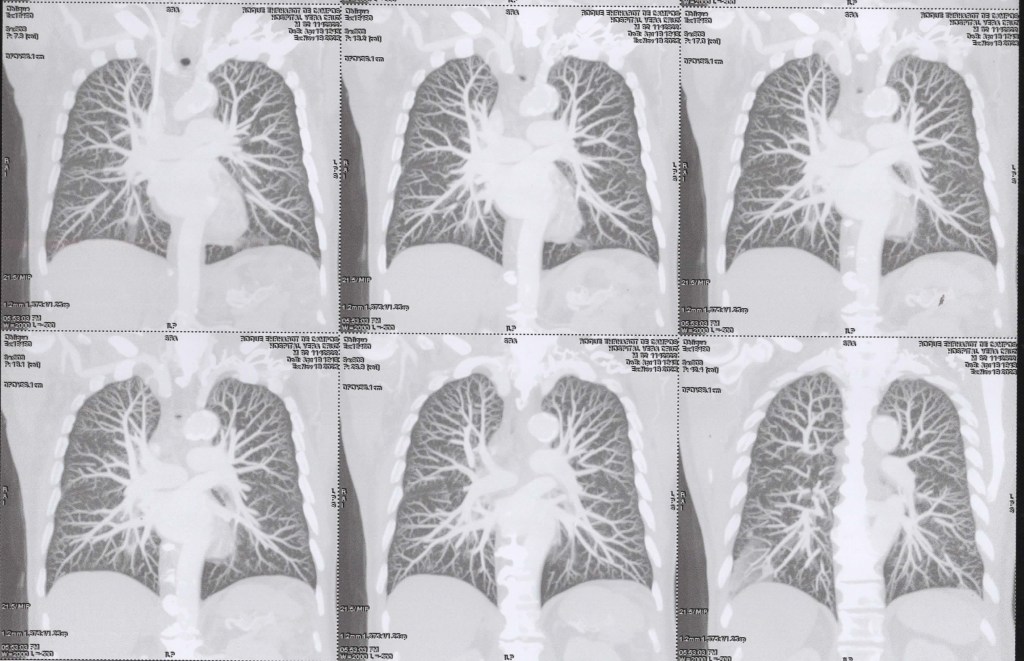

(TC) de Tórax com cortes coronais (vista frontal), em janela pulmonar, com técnica MIP (Maximum Intensity Projection).